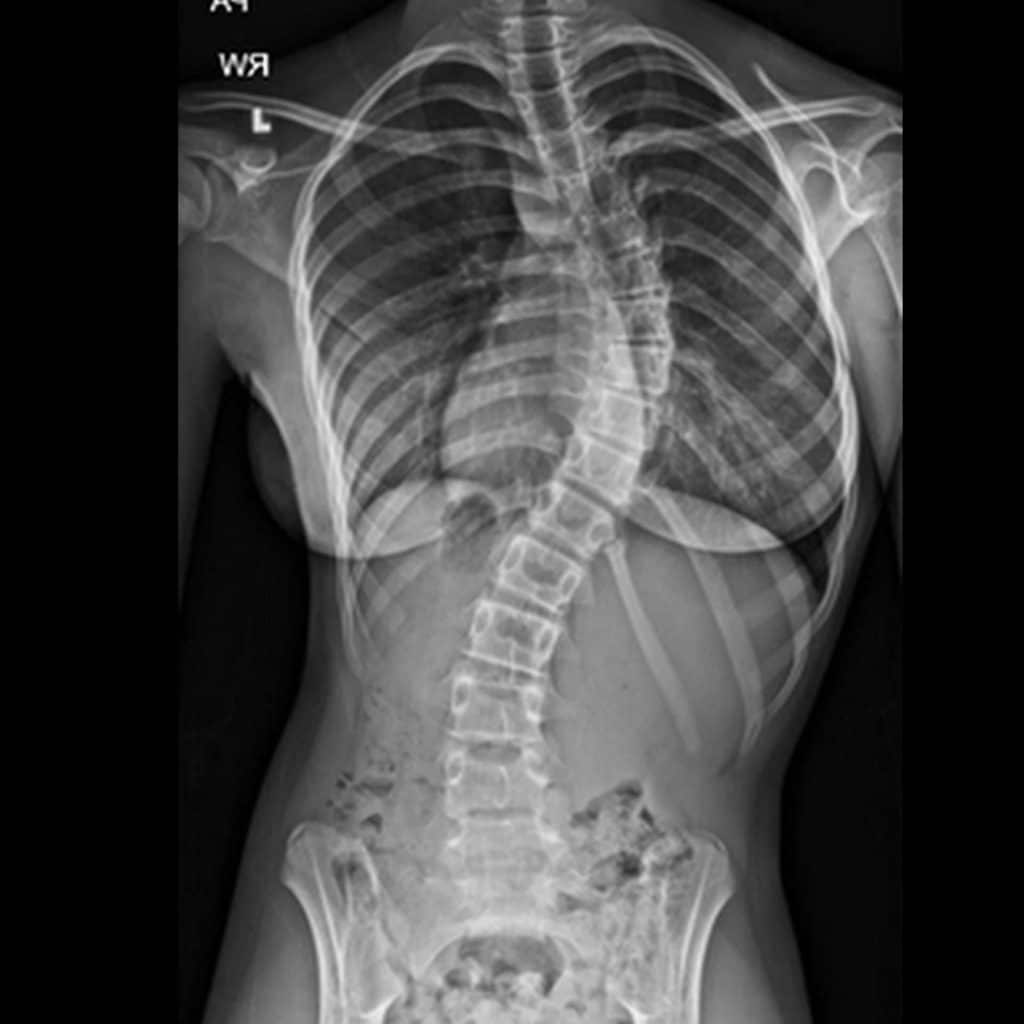

In my studies I’ve learned about different types of scoliosis and causes behind them. Scoliosis can be caused by a number of things like congenital diseases, abnormal vertebral formation or degeneration. Often, we see patients in our clinic with scoliosis that has no cause at all. This is called Idiopathic Scoliosis. For scoliosis to be idiopathic, all other possible causes have been ruled out and, for some reason, the spine has developed curves and twists without apparent cause.

In any case, all forms of scoliosis follow what is called “The Vicious Cycle.” It begins with wedging of the vertebrae and discs which leads to spinal curvature. This curvature gives way to asymmetric loading where one side of the spine takes on more pressure or stress than the other. Because of this asymmetric loading, the spine and muscles undergo asymmetric growth, which further wedges the discs and vertebrae starting the whole cycle over again. Without intervention of some kind, this cycle goes unchecked and causes progression of the curve. What we do in physical therapy using The Schroth Method, is step in at the moment of asymmetric load and disrupt this cycle.